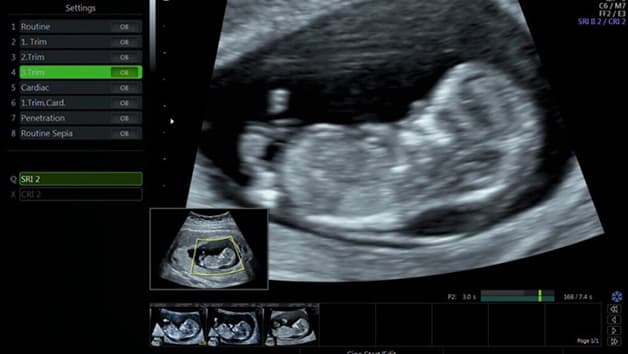

Khám thai đo độ mờ da gáy được thực hiện bằng phương pháp siêu âm từ tuần 11 đến 13 của thai kỳ

Siêu âm đo độ mờ da gáy là một trong số những biện pháp sàng lọc dị tật thai nhi từ sớm, cụ thể là giúp phát hiện hội chứng Down ở trẻ. Khi tiến hành phương pháp siêu âm, bác sĩ sẽ đo chiều dài từ đỉnh đầu đến cuối xương sống của thai nhi, sau đó kiểm tra độ mờ da gáy. Phần màu trắng trên màn hình siêu âm chính là phần da của bé. Phần dịch tích tụ phía sau gáy được hiểu thị trên hình ảnh là phần màu đen. Khoảng mờ sau gáy được thể hiện dưới hình ảnh một đường trắng xuất hiện ngay sau gáy của thai nhi. Kỹ thuật đo độ mờ da gáy chủ yếu được thưc hiện qua siêu âm đường bụng. Tuy nhiên trong một số trường hợp, có thể kết hợp với siêu âm đường âm đạo để đạt kết quả chính xác hơn. Quá trình này không gây bất kì nguy hiểm nào cho mẹ và bé.

Để đo độ mờ da gáy của thai nhi, các mẹ cần thực hiện phương pháp siêu âm thai. Bác sĩ sẽ sử dụng một đầu dò, gel chuyên dụng bôi lên phần bụng của mẹ bầu, sau đó di chuyển đầu dò trên thành bụng để tiến hành kiểm tra tình trạng thai nhi. Thông qua những sóng âm tần số cao, hình ảnh hiển thị rõ nét trên màn hình máy siêu âm, giúp bác sĩ có thể xác định được chính xác vị trí của thai, tiến hành đo độ mờ da gáy.

Đầu tiên, để xác định được chính xác tuổi thai, bác sĩ sẽ tiến hành đo chiều dài tính từ đỉnh đầu đến cuối xương sống của thai. Sau đó, bác sĩ sẽ theo dõi khoảng mờ nằm ở sau gáy thai nhi, khi các vùng xung quanh hiển thị với màu sắc tối hơn. Dựa vào tính toán tuổi thai, bác sĩ sẽ cho mẹ bầu biết thai nhi có đang gặp nguy cơ dị tật do bất thường về nhiễm sắc thể hay không.